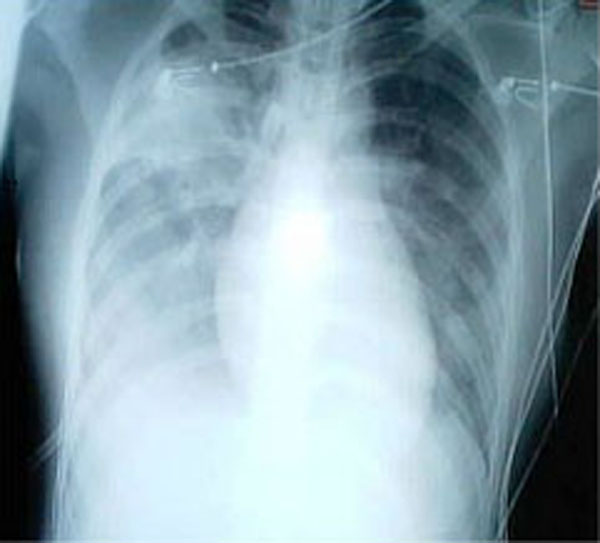

Two people have died and five others have been hospitalized in a mysterious cluster of respiratory illnesses in southeast Alabama, state health officials said.

The victims, all adults, had symptoms including fever, cough and shortness of breath, but the cause of the illnesses is unknown, said Dr. Mary McIntyre, the acting state epidemiologist for the Alabama Department of Public Health. The hospital is using respiratory precautions, which include requiring staff to wear special N95 masks that reduce the chance of infection.

State health officials have collected and analyzed samples of specimens from all patients. So far, one sample has tested positive for H1N1 influenza A, but it’s not clear that that is behind the unusual illnesses. There’s no evidence of other kinds of flu, including the H7N9 strain that has caused illness and death in China, McIntyre said.